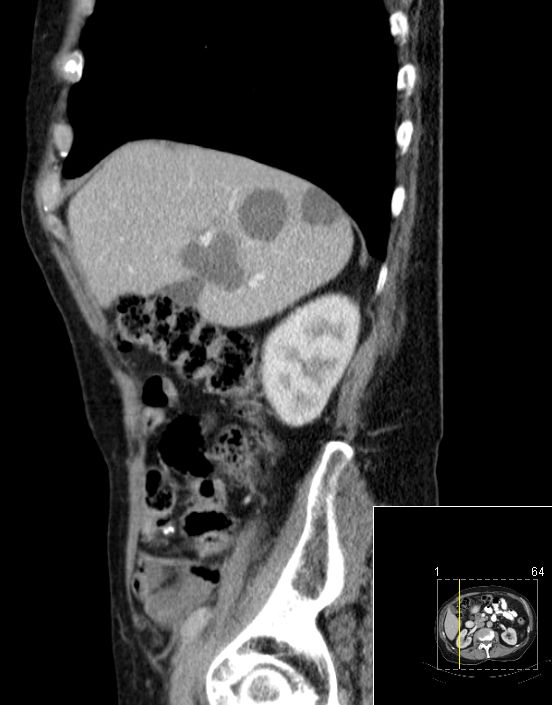

| CT | 75-jähriger Mann, der vor einem Jahr ein Rektum-Karzinom hatte: ypT3a ypN1b(2/18) Mo Li Vo G2. 5x5Gy.

Anteriore Rektumresektion, 4x 5-FU. Jetzt Lebermetastasen.

![]() |